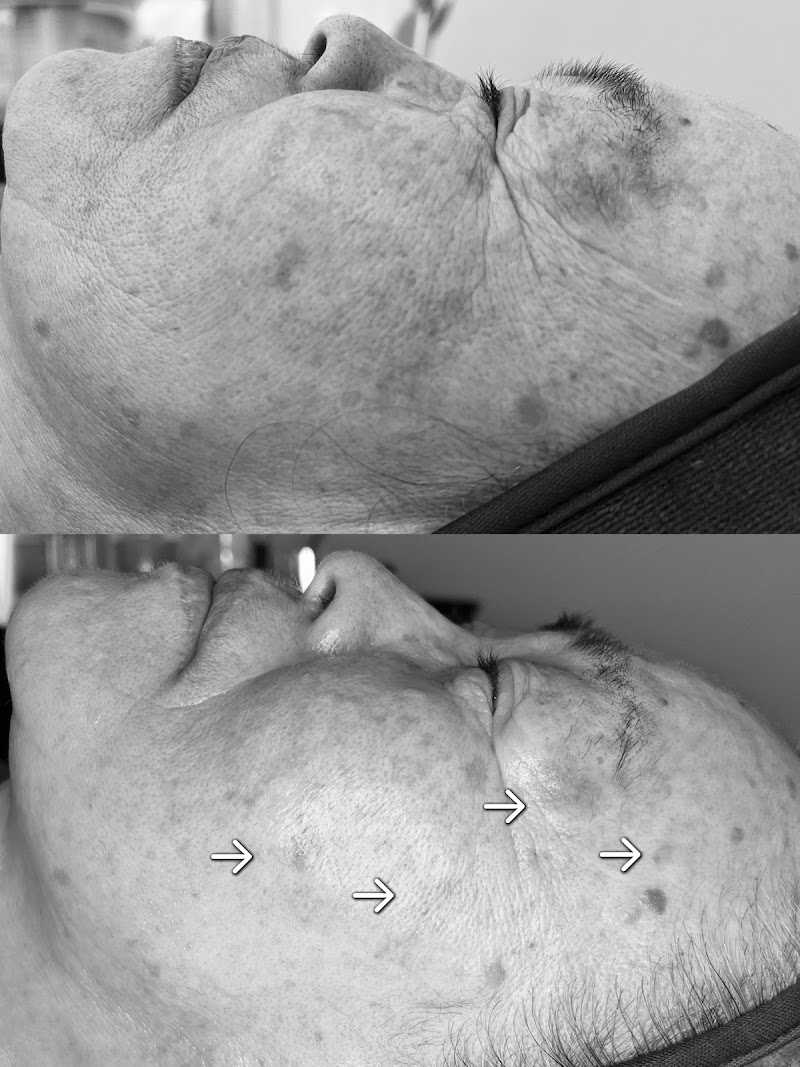

ラミピール施術後、驚くほどの肌のリフトアップ効果が実感できました。

こちらにはラミピールで2回ご利用させて頂きました。私は肌が弱くてピーリングのようなものを避けてきたんですが、やってみて正解でした!!1回目でも驚きの変化!!!シミも薄くなったのと、肌のトーンアップ、毛穴の開きもあまり気にならなくなりました。化粧のノリも全然違います!初めてエステでここまで効果を感じました!そして、もっと驚いたのが2回目の施術後の変わりようです!!次の日からとにかく肌の明るさが明るくなり、目尻の皺、ほとんど消えました!肌のハリ、触り心地、化粧ののり、シミ、毛穴、そしてリフトアップ効果もあるのかフェイスラインがスッキリしました!2回目の施術から1週間経ちますが日に日に肌の調子が良くなっていくので、毎日鏡を見るのが楽しみです!!スタッフの方の施術も丁寧でとてもリラックスしながら施術を受けることができます。本当に感謝しかないです。ありがとうございます。何をやっても変わらなかった肌だったんですが、ここまで変わったのを実感できたのは初めてです!本当にオススメです!!

肌が乾燥し弛んでいた顔がリフトアップし、終わった後は別人のように色が白くなっていたのに驚きました。1回の施術でここまでなるとは思ってみなかったのでまた、続けて見たいと思いました。